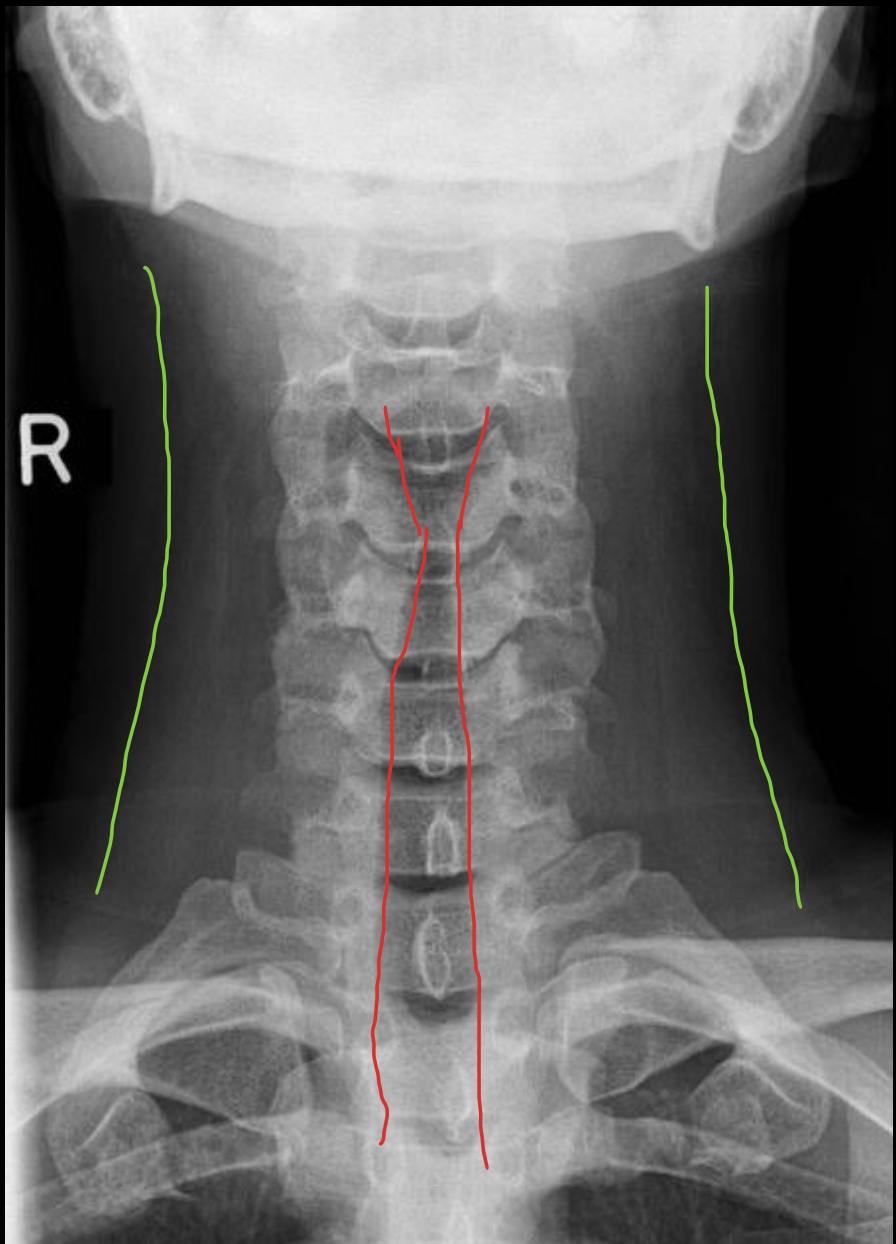

气管

Trachea